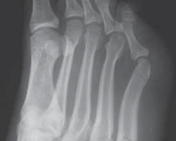

Let us begin by establishing a rigorous definition of the pathology. A true Jones fracture represents an acute injury occurring specifically at the metaphyseal–diaphyseal junction of the fifth metatarsal. Crucially, as originally described and later refined in the orthopedic literature, the fracture line must not extend distal to the fourth–fifth intermetatarsal articulation. This strict anatomical distinction is vital for accurate diagnosis, as it differentiates the Jones fracture from proximal tuberosity avulsion fractures (pseudo-Jones fractures) and more distal diaphyseal stress fractures, both of which possess distinct natural histories, healing potentials, and treatment algorithms.

To guide our clinical decision-making and surgical strategy, we rely heavily on the Torg classification system. This framework categorizes fifth metatarsal base fractures into three distinct subsets based on chronicity, radiographic appearance, and healing potential. Type 1 represents the acute fracture. Radiographically, these lesions exhibit sharp, well-defined fracture margins without any evidence of intramedullary sclerosis, and the fracture typically involves only the lateral cortex initially, though it may be complete. Type 2 describes a delayed union. In these cases, the fracture line involves both cortices, and we observe associated periosteal new bone formation, a widening or cystic appearance of the fracture line, and early intramedullary sclerosis indicating a stalled biological healing response.

Finally, Type 3 denotes a frank nonunion. This represents a complete failure of the osteogenic process. Radiographs will demonstrate significant bone resorption with a wide radiolucent gap at the fracture site, and the medullary canal will be completely obliterated by dense sclerotic bone. Nonoperative treatment of acute Jones fractures, particularly in high-demand individuals, is associated with an unacceptably high risk of progression from Type 1 to Types 2 and 3. This progression is primarily dictated by the watershed blood supply at this critical junction, necessitating surgical intervention to alter the mechanical environment and stimulate osteogenesis.

Standard radiographic evaluation must include high-quality anteroposterior (AP), lateral, and oblique views of the foot. The AP view is critical for assessing the fracture gap and the medial-lateral diameter of the medullary canal. The lateral view is essential for evaluating the dorsal-plantar canal diameter and, most importantly, the plantar bow of the metatarsal shaft. The oblique view provides the best visualization of the metaphyseal-diaphyseal junction and the fourth-fifth intermetatarsal articulation. In cases of delayed union, nonunion, or complex fracture patterns, a computed tomography (CT) scan is highly recommended to assess bone stock, exact canal dimensions, and the presence of cystic changes that might necessitate bone grafting.